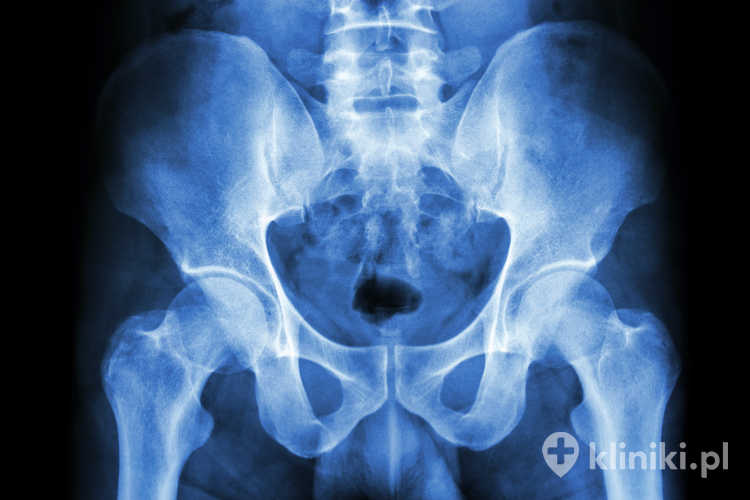

Staw biodrowy jest stawem kulistym, uformowanym przez głowę kości udowej i panewkę kości miednicznej. Staw ten jest wzmocniony systemem więzadeł, a jego budowa umożliwia wykonywanie ruchów takich jak prostowanie, zginanie, przywodzenie, odwodzenie czy rotacja.